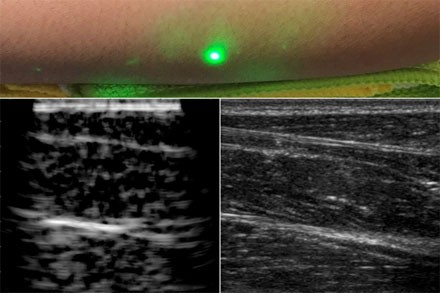

據(jù)外媒報道,12月24日,麻省理工學(xué)院的工程師設(shè)計了一種常規(guī)超聲成像的替代方法,這種方法不需要與身體接觸,可用于無法忍受探針進入身體的患者,如嬰兒、燒傷患者或皮膚敏感的患者。在掃描志愿者前臂的試驗中,研究人員能夠觀察到皮膚以下約5厘米處常見的組織特征,如肌肉、脂肪和骨骼。這些圖像與傳統(tǒng)的超聲波相當(dāng),是使用聚焦在半米外的遠程激光產(chǎn)生的。由于聲波比光傳播到體內(nèi)的距離要長,因此研究人員首先研究如何在皮膚表面將激光束的光轉(zhuǎn)換成聲波,以便在體內(nèi)成像更深。該團隊選擇了1550 nm激光器,該波長很容易被水吸收,并且對眼睛和皮膚都是安全的,有很大的安全邊際。由于皮膚主要由水組成,因此研究小組認為皮膚應(yīng)有效吸收該波長,并且它會隨著反應(yīng)而升溫和膨脹。當(dāng)它振蕩回到正常狀態(tài)時,可以預(yù)期皮膚會產(chǎn)生通過身體傳播的聲波。研究人員用一個1550nm的脈沖激光產(chǎn)生聲波,用另一個調(diào)諧到相同波長的連續(xù)激光遠程探測反射聲波,驗證了這一想法。第二個激光是一個運動探測器,它測量了聲波從肌肉、脂肪和其他組織反射到皮膚表面所引起的振動。反射聲波產(chǎn)生的皮膚表面運動引起激光頻率的可測量變化,通過對全身激光進行機械掃描,研究人員能夠在不同的位置獲取數(shù)據(jù),并生成該區(qū)域的圖像。一種新的超聲波技術(shù)利用激光在皮膚下產(chǎn)生圖像,而不像傳統(tǒng)的超聲波探頭那樣與皮膚接觸。新的激光超聲技術(shù)被用來產(chǎn)生一個人類前臂的圖像(左),這也是使用常規(guī)超聲成像(右)。由X.Zhang等人提供。研究人員首先利用這一新的裝置,將金屬物體嵌入一個類似皮膚含水量的明膠模具中進行成像。他們用商業(yè)超聲探頭對同一明膠成像,發(fā)現(xiàn)兩幅圖像相似。然后,他們對切除的動物組織(在本例中是豬皮)進行成像,發(fā)現(xiàn)激光超聲可以區(qū)分細微的特征,如肌肉、脂肪和骨骼之間的界限。最后,研究小組利用麻省理工學(xué)院人類實驗委員會批準(zhǔn)的方案,在人類身上進行了第一次激光超聲實驗。在掃描了幾名健康志愿者的前臂...